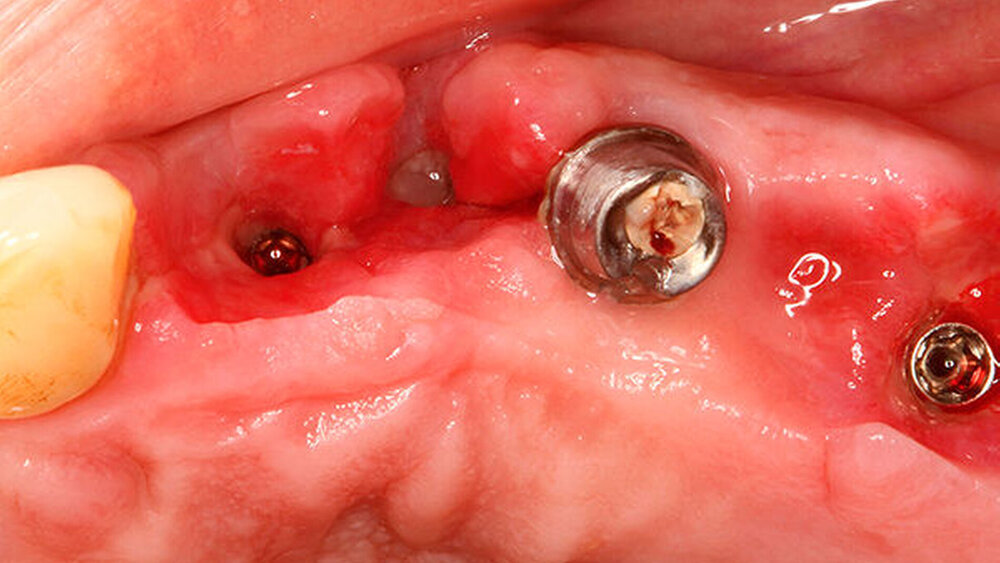

Wir haben extrahiert, dann die Implantate inseriert, direkt nach der Implantation die Scanbodys aufgesetzt, den optischen Abdruck genommen und das Langzeitprovisorium aus PMMA verschraubt. Dass die Innenverbindung immer die gleiche ist, hilft dabei sehr. Eine Prothetik passt tatsächlich auf alle Implantate.

Ich auch, entsprechend konservativ sieht unser Konzept aus, nach dem ich auch meine Frau behandeln würde. Ich ziehe den nicht erhaltungswürdigen Zahn, lege Kollagen ein, kein KEM, um das Blutkoagulum zu stützen. Nach sechs Wochen setze ich entsprechend den prothetischen Rahmenbedingungen im Frontzahnbereich das Implantat und nach zwölf Wochen im Seitenzahnbereich. Die bukkale Lamelle stabilisiere ich mit einem resorptionsstabilen KEM. Dann erfolgt die Abdeckung mit einer Membran (GBR). Für dieses Vorgehen gibt es sehr schöne Zehnjahresergebnisse von Chappuis et al. aus der Berner Arbeitsgruppe, die letztes Jahr veröffentlicht wurden. Für diese Indikation würde ich auch ein BLX verwenden.